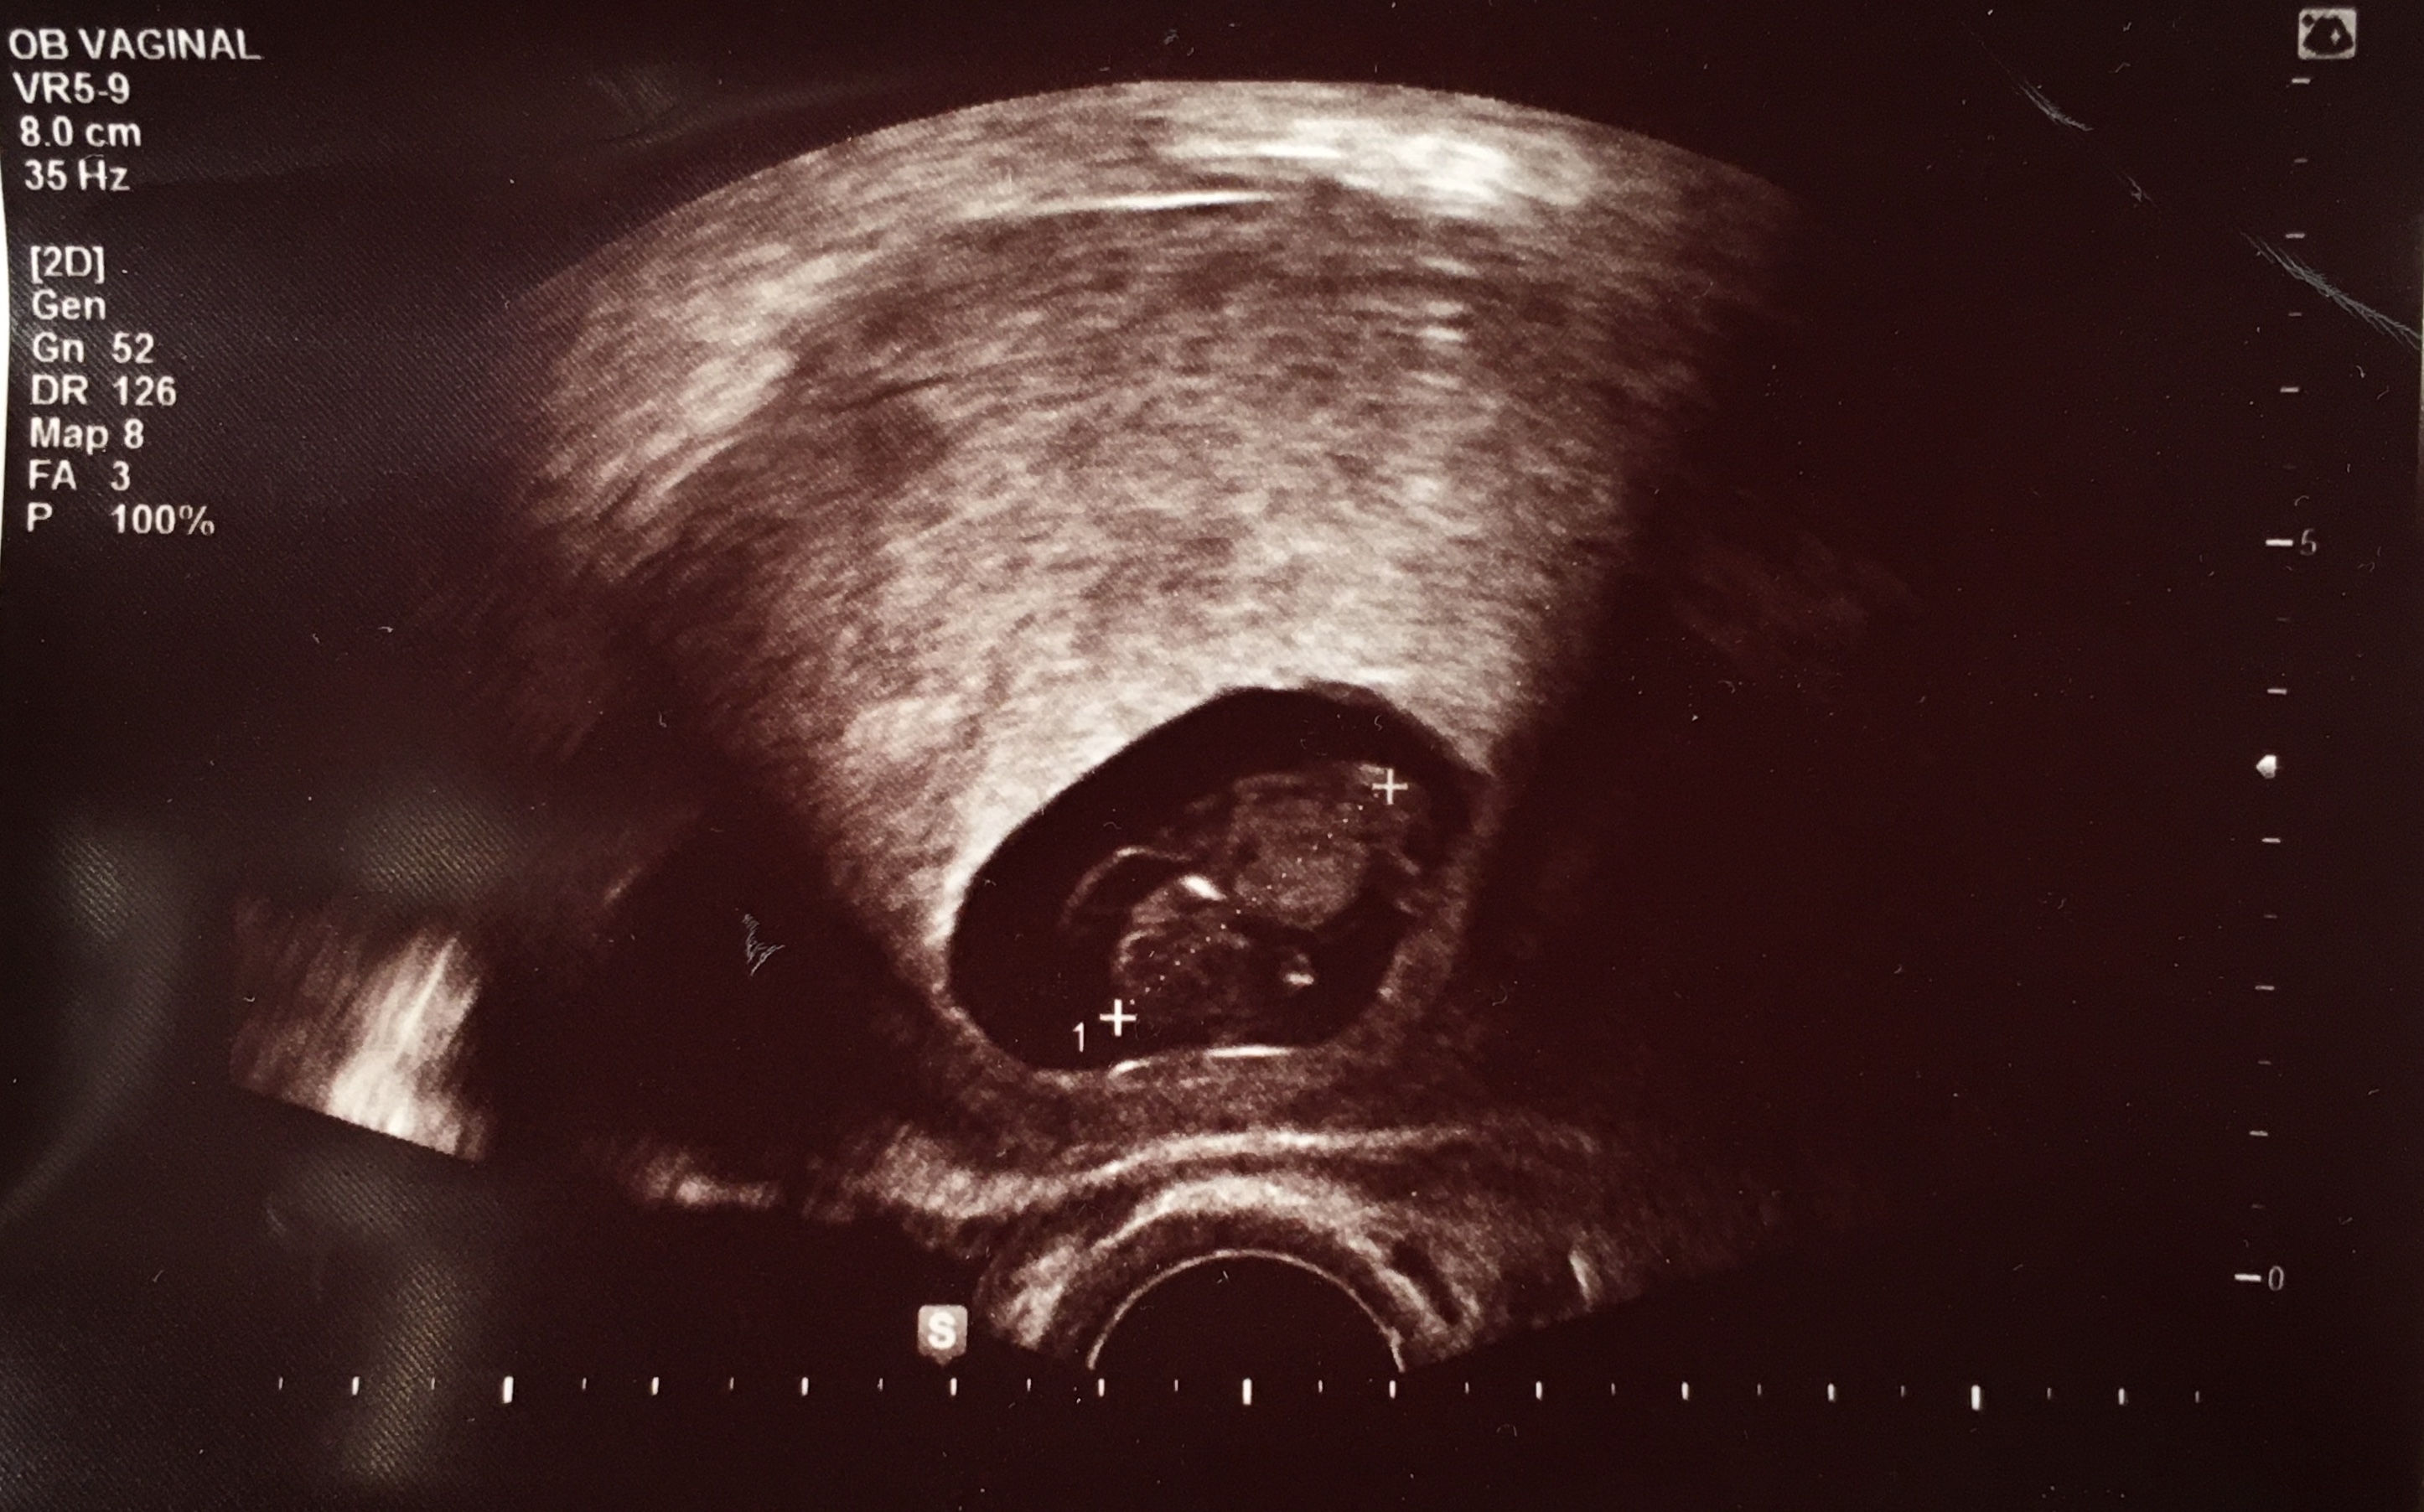

계류유산이란 자궁경부가 닫혀 태아가 남아 있는 유산을 말한다. 예상치 못한 이별인 만큼, 큰 아픔이 될 것입니다. 보류 중인 유산의 가장 널리 알려진 원인은 염색체나 수정란의 변형입니다.

유산이 발생할 확률은 약 10~15%로 결코 낮지 않습니다. 하지만 전조증상이나 발생 후 증상이 거의 없어 미리 알거나 대비하는 것이 쉽지 않다. 그러므로 그것은 어머니의 책임이나 잘못이 아닙니다.